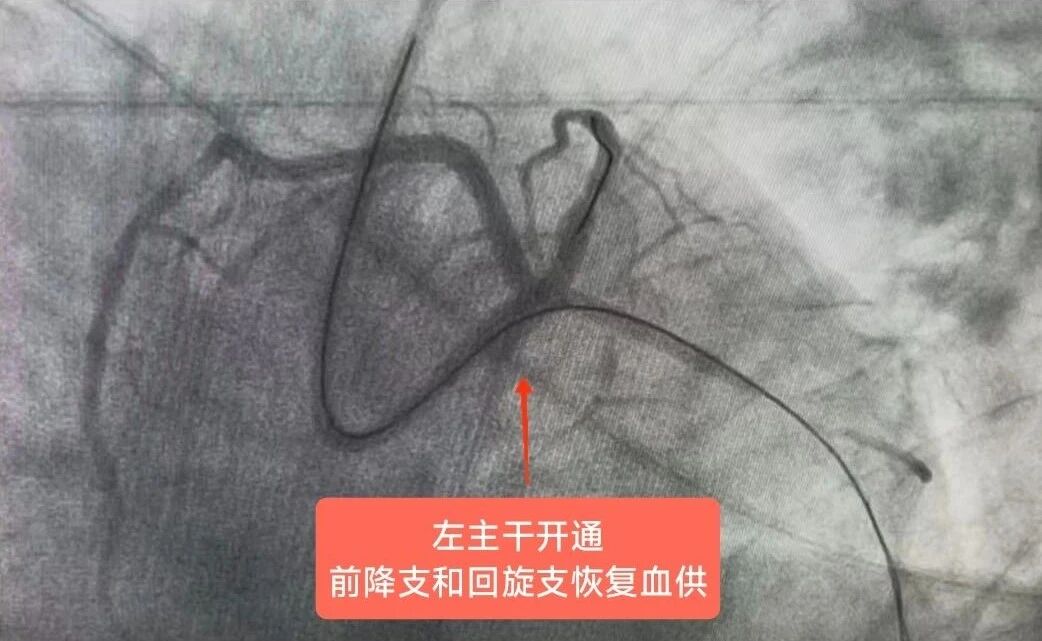

在疏通血管的过程中,钟先生还出现了血压下降、呼吸困难等危险情况。关键时刻,团队紧急启用IABP技术,李驹植入IABP球囊,改善冠状动脉血流,稳住患者血压,为营救患者争取时间,之后迅速植入支架,开通血管,稳定钟先生心脏血液循环。经过近3小时的紧张手术,钟先生的堵塞血管成功疏通,生命体征逐渐稳定,随后转入危急重症中心(ICU)进一步治疗。

冠脉造影显示患者左主干血管开通

血管开通显示慢血流